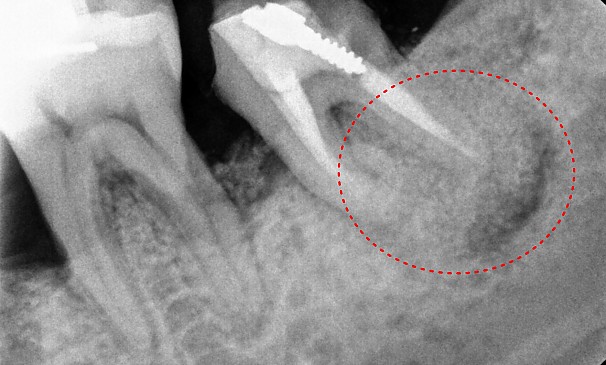

유OO님 전후사진 | 치료 기간 : 4주

치료 후